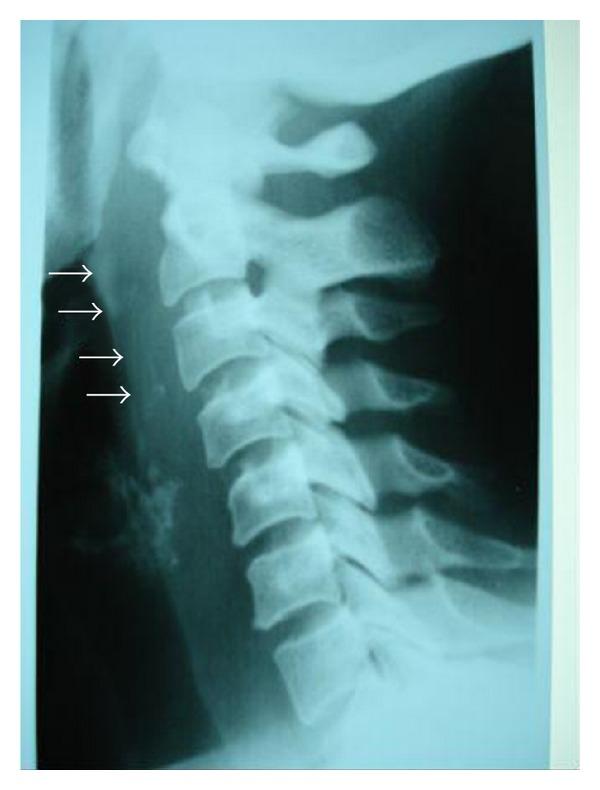

Retropharyngeal abscesses are rare in adults. They occur mostly in immunocompromised patients or as a foreign body complication. We report 5 cases of retropharyngeal abscess collected in the ENT Department of CHU Mohammed VI of Marrakech, during a two-year period (December 2008 to December 2009). Local trauma by foreign body ingestion was the aetiology in four patients. The presenting symptoms, for all patients, were fever, odynophagia, torticollis, and trismus, and the clinical examination showed bulging of the posterior wall of the oropharynx. The radiography of cervical spine showed prevertebral thickening in all cases, this thickening was associated with an aspect of vertebral lysis of the fourth cervical vertebra in one case. A CT scan was performed in all our cases and showed features of retropharyngeal abscess which was associated, in one case, with spondylodiscitis. The biological assessment found one case of diabetes. The intradermal reaction to the tuberculin was clearly positive in one case. Endobuccal abscess puncture was practiced in 4 cases; only one organism was identified by culture: Staphylococcus aureus treatment was based on triple intravenous antibiotics and anti-Koch's therapy (in one case), and the surgical drainage under general anesthesia was also performed in the case of the diabetes patient which required also the correction of hyperglycemia in intensive care unit. The outcome was good in all our patients. The diagnosis of retropharyngeal abscess can be difficult and one must seek a comorbidity; a tuberculosis aetiology must be considered in countries with a high prevalence. The management of these cases is based on antibiotics and surgical drainage.

咽后脓肿在成人中较为罕见。它们大多发生在免疫功能低下的患者中,或作为异物并发症出现。我们报告了在马拉喀什穆罕默德六世大学医院耳鼻喉科在两年期间(2008年12月至2009年12月)收集的5例咽后脓肿病例。4例患者的病因是异物吞食导致的局部创伤。所有患者的主要症状为发热、吞咽痛、斜颈和牙关紧闭,临床检查显示口咽后壁膨出。颈椎X线片在所有病例中均显示椎体前增厚,其中1例增厚与第四颈椎椎体溶解表现相关。我们所有病例均进行了CT扫描,显示咽后脓肿特征,其中1例与脊椎椎间盘炎相关。生物学评估发现1例糖尿病患者。1例患者结核菌素皮内反应明显阳性。4例患者进行了口内脓肿穿刺;培养仅鉴定出1种微生物:金黄色葡萄球菌。治疗基于三联静脉抗生素和抗结核治疗(1例),对于糖尿病患者还在全身麻醉下进行了手术引流,该患者在重症监护病房还需要纠正高血糖。我们所有患者的预后良好。咽后脓肿的诊断可能困难,必须寻找合并症;在患病率高的国家必须考虑结核病因。这些病例的管理基于抗生素和手术引流。